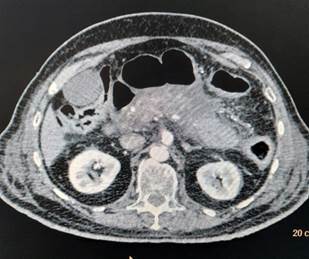

Her laboratory investigations revealed the following serum amylase 899 U/L, lipase 710 U/L, total leucocyte count 11500, Hb 14.1 g/dl, platelet count 1,90,000, serum aspartate aminotransferase 66 U/l, alanine aminotransferase 46 U/L, alkaline phosphatase 99 U/L, bilirubin total 0.9 mg/dl, blood urea nitrogen 27mg/dl, creatinine 0.5mg/dl, Na + 140 meq/l, K+ 3.5 meq/l, Ca 2+ 9.5mg/dl, phosphorus 3.5mg/dl. CT scan

Figure 2: BH: Abdominal CT (Axial) – Kidneys and Bowel Loops Visualized

of abdomen (Figure 1) showed bulky/ enlarged and heterogenous pancreas with non-enhancing necrotic areas within it. Tail is poorly visualized (likely necrotic). Peripancreatic fat stranding with peripancreatic fluid is noted – features suggestive of acute necrotizing pancreatitis. As a routine protocol for admission in intensive care unit during this covid era, her nasopharyngeal and oropharyngeal swab was sent for COVID-19 testing by reverse transcriptase polymerase chain reaction (RT-PCR) which came out to be positive. Diagnosis of acute viral pancreatitis, COVID-19 induced, was kept. She was admitted in COVID-19 isolation ward and treated symptomatically with bowl rest, intravenous fluids, analgesia and empirical antibiotics. She was managed conservatively and discharged in hemodynamically stable condition after 1 week.